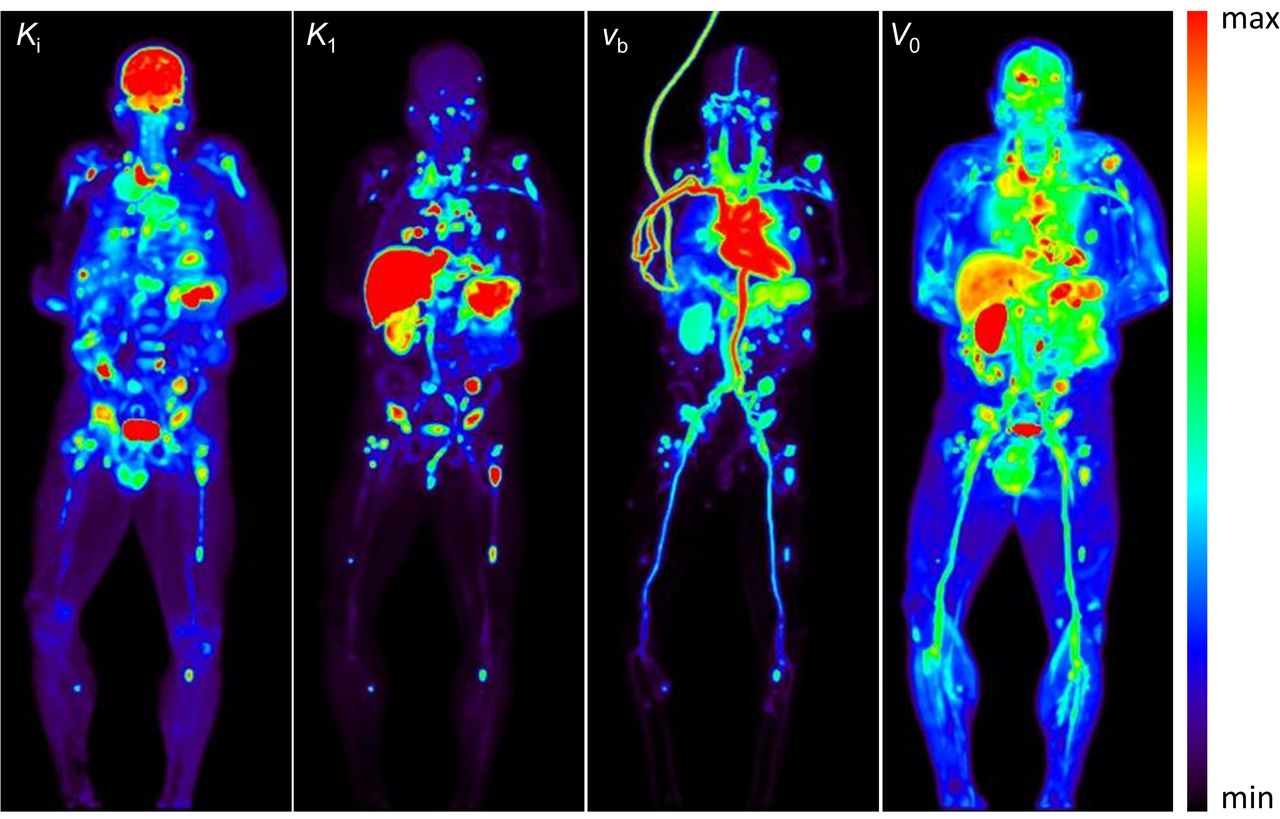

PSMA PET-CT Accurately Detects Prostate Cancer Spread - NCI PET Scan: What It Is, Types, Purpose, Procedure & Results PET/MRI biomarkers guide personalized treatment for patients with pancreatic cancer - Mayo Clinic News Network PSMA-PET is rapidly changing the standard of care for prostate cancer patients | Pet Scan Cancer